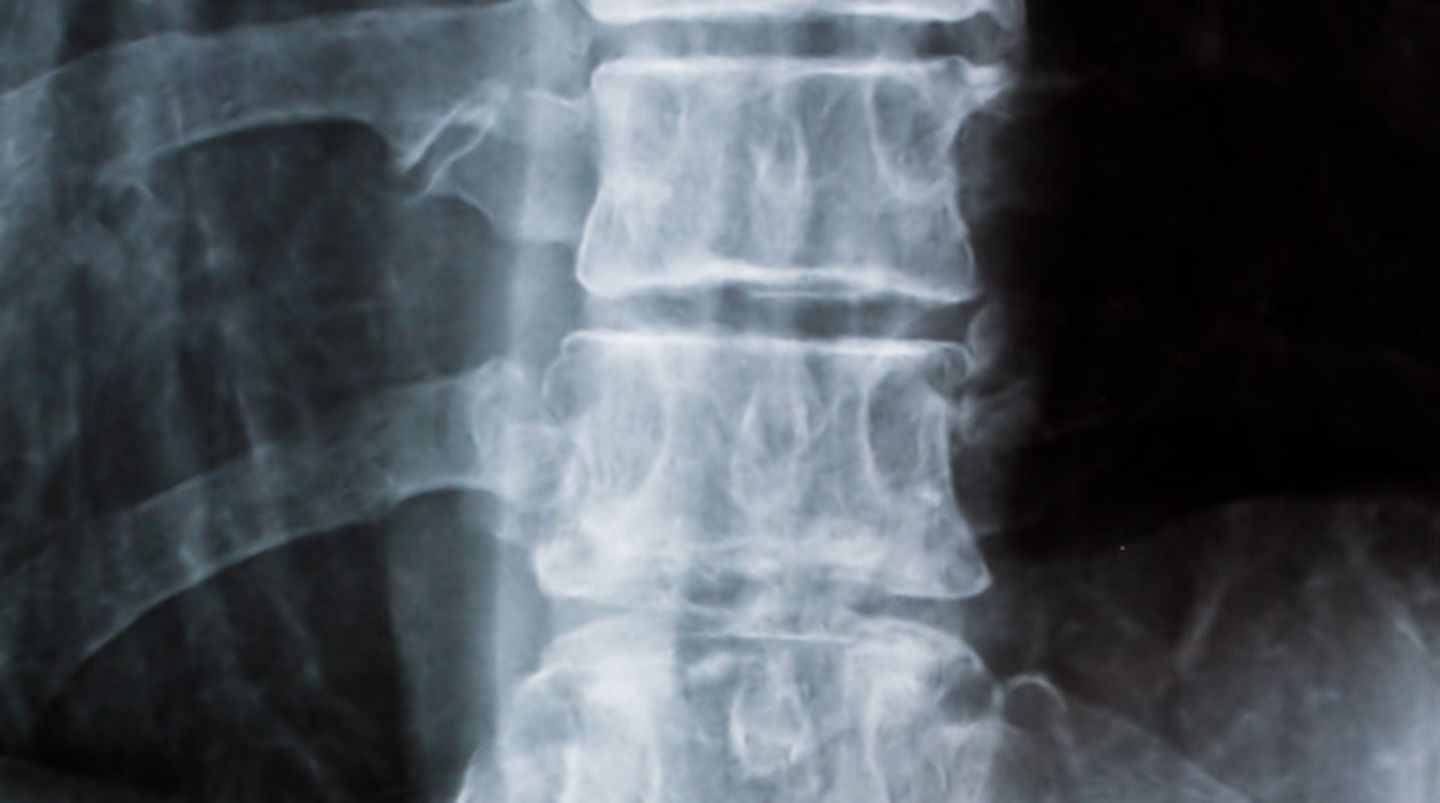

• Tag der Rückengesundheit: Die zehn schlimmsten Dinge für die Wirbelsäule

Zur Galerie Tag der Rückengesundheit: Die zehn schlimmsten Dinge für die Wirbelsäule

Platz 9: ein Arzt    Jede ärztliche Diagnose, sei sie auch noch so unerheblich, verstärkt das Problem: Der Rückenschmerz setzt sich fest - schließlich hat der Arzt ja etwas gefunden.  Wie gut kennen Sie sich mit Ihrem Rücken aus? Ihr Wissen können Sie hier testen

Jede ärztliche Diagnose, sei sie auch noch so unerheblich, verstärkt das Problem: Der Rückenschmerz setzt sich fest - schließlich hat der Arzt ja etwas gefunden.